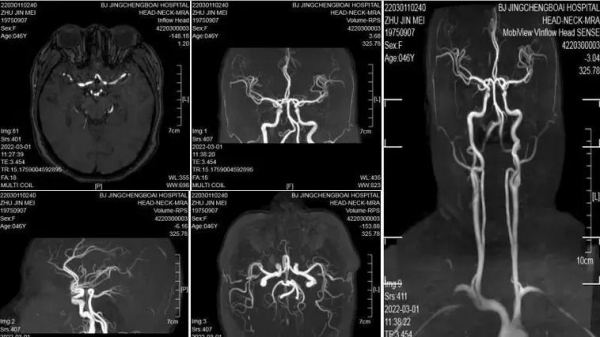

好消息是,现代医学条件下,脑动脉瘤完全可以通过影像学筛查出来。

· 磁共振血管成像(MRA):无创、无辐射,适合体检筛查

· CT血管造影(CTA):对直径<3mm的小动脉瘤也能识别

· 数字减影血管造影(DSA):被称为"金标准",分辨率更高,但入侵性较强